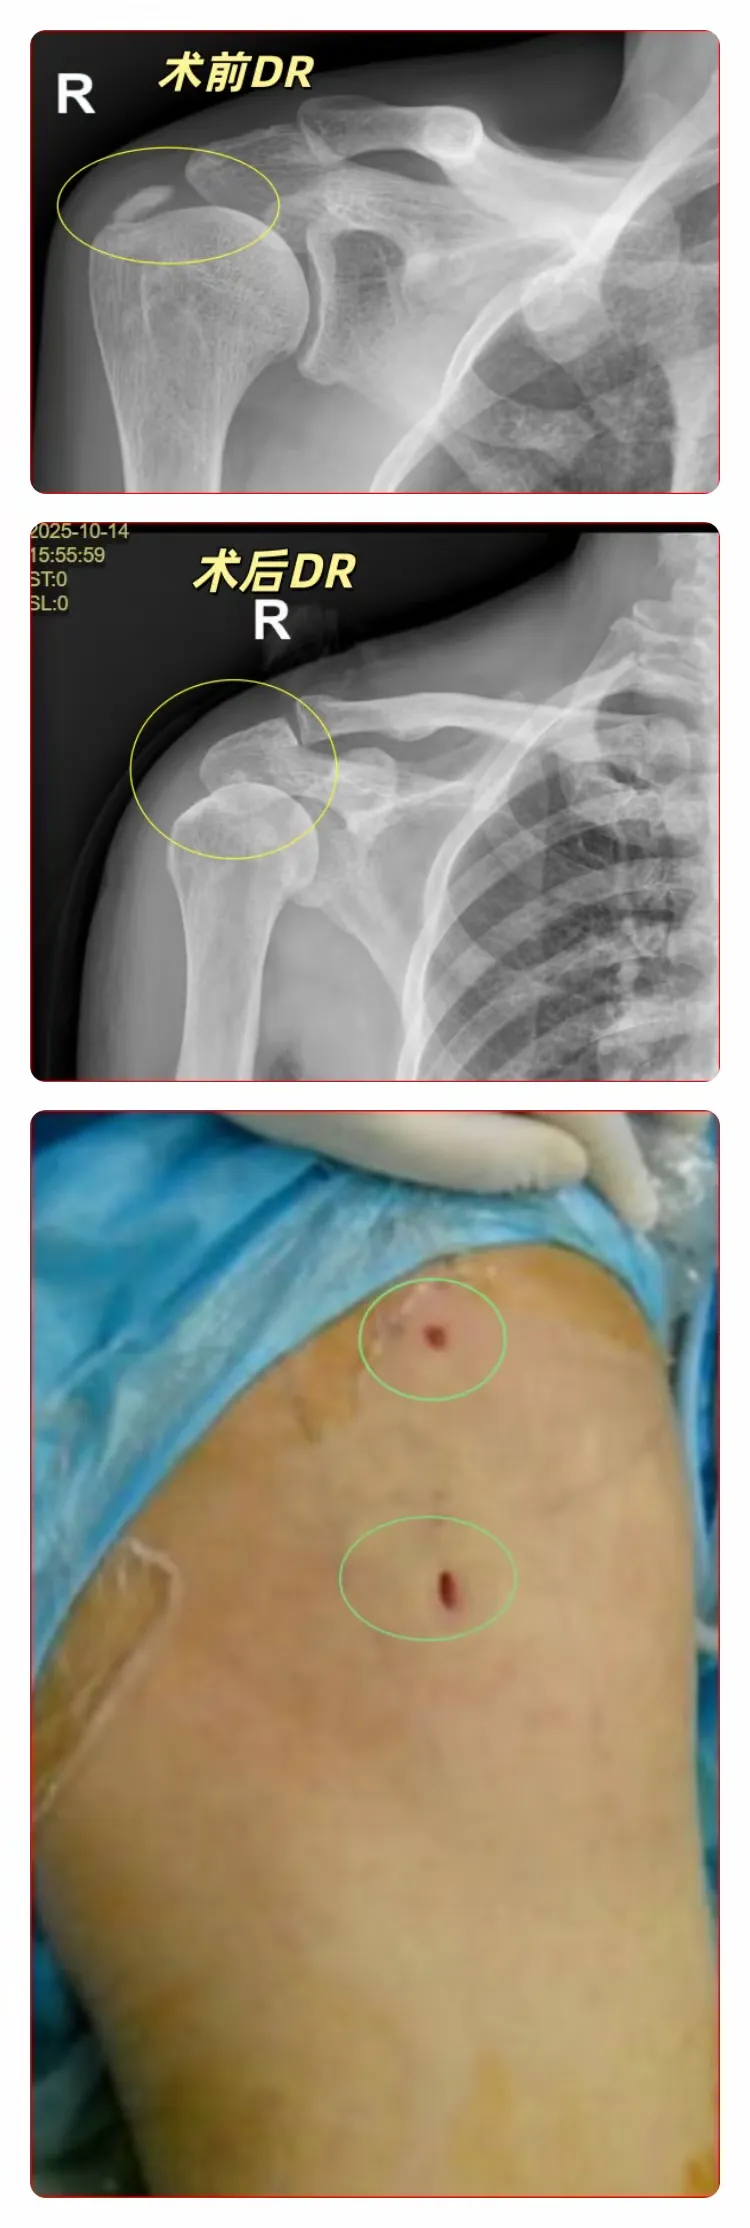

该院骨科戴冠东主任医师接诊后,第一时间为患者完善相关检查,经详细诊断,确定患者为“肩袖钙化性肌腱炎”,需住院接受手术治疗。

骨科医疗团队对患者的情况进行了讨论,针对患者冈上肌肌腱钙化灶明显,炎症反应较重的情况,最终确定手术方案——肩关节镜下冈上肌肌腱钙化灶清除、肩峰成型术。患者手术指征明确,可以进行关节镜微创手术,创伤小,住院时间短,有利于减轻患者痛苦。

手术顺利完成后,患者(张女士)的肩关节疼痛得到显著缓解。“肩关节镜微创手术,只需要几个小切口,与传统切开手术相比,创伤小,恢复快,住院时间短,张女士后期经过康复锻炼后,将逐渐恢复肩关节功能,恢复日常生活。”戴冠东主任介绍道。